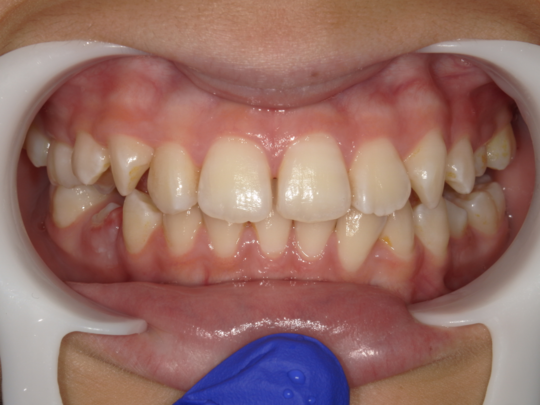

治療後

治療の副作用(リスク)歯の動き方には個人差があり、予想された治療期間が延長する可能性があります。。床矯正の使用状況、矯正歯科治療には患者さんの協力が必要であり、それらが治療結果や治療期間に影響します2次矯正が必要になる場合もあります。

治療の副作用(リスク)歯の動き方には個人差があり、予想された治療期間が延長する可能性があります。。床矯正の使用状況、矯正歯科治療には患者さんの協力が必要であり、それらが治療結果や治療期間に影響します。2次矯正が必要になる場合もあります。